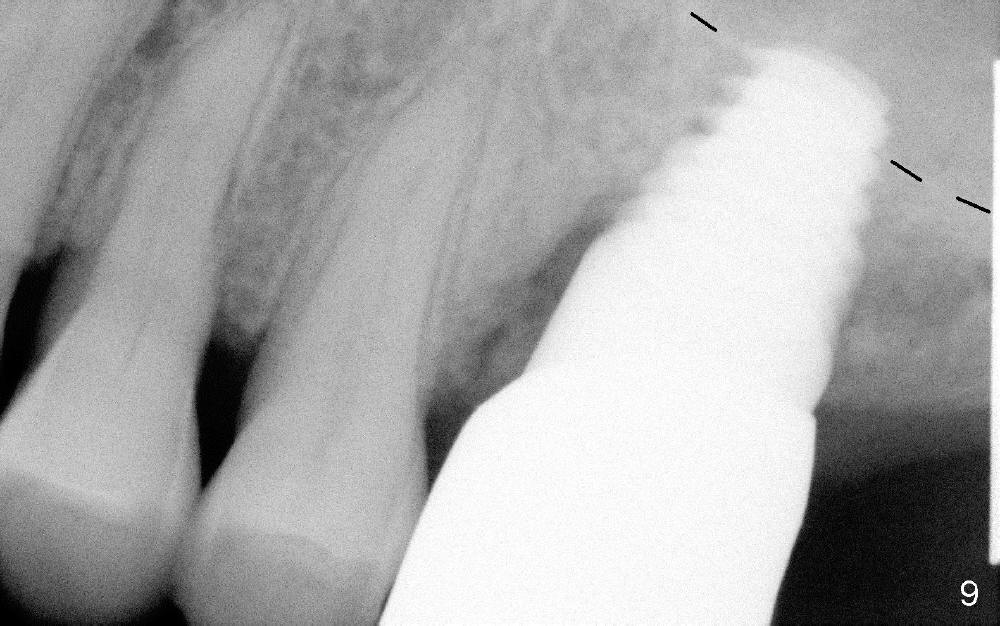

Crown is cemented 5.5 months postop.(Fig.9) and has been in function for more than 34 months (Fig.10,11).